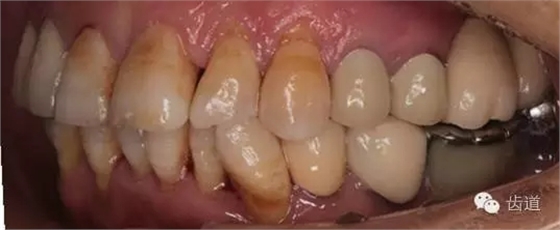

1、全口正面觀